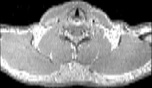

Visible Human male: Sectio transversalis 1262

CT

NMR

Pd T1 T2